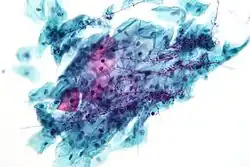

Micrograph of a normal pap smear -

Micrograph of a Pap test showing a low-grade intraepithelial lesion (LSIL) and benign endocervical mucosa. Pap stain. -